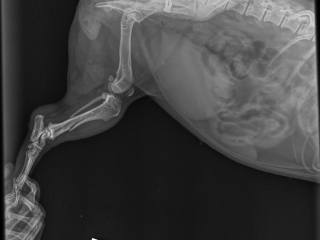

Наша любимая собака очень заболела из-за того что сильно упала с кресла ночью. Она была жизнерадостной, никогда никого не кусала, любила детей,

Помогите пожалуйста, кто чем может. Нужна срочная операция собаке. Джек-рассел Кроха. Ей всего 3 годика. Она член семьи, подруге подарил ее муж и спустя 2 месяца погиб. Подруга осталась одна с 3 детьми на руках. Что могли собрали по друзьям, но все равно не хватает еще 50000. Не оставайтесь...

Люди добрые,помогите пожалуйста. Два дня назад,гулял с собакой.Собака вырвалась с цепи,попала под машину.Врачи сказали нужна операция.Питомец очень дорого,8 лет как живет со мной.Не хватает 2000р на операцию.Кому не сложно помогите.Студент,учусь не в родном городе.С финансами проблемы.Дай вам бог...

Так вышло, что мой любимый питомец шпиц начал болеть в ноябре 2016года. Рвота, понос с кровью, отказ от еды. Начавшееся лечение в ветклинике (капельницы, уколы,таблетки) не приносили результата.... Но потом любимка поправился, начал кушать, набрал вес, стал снова веселым....всего на два месяца. в...